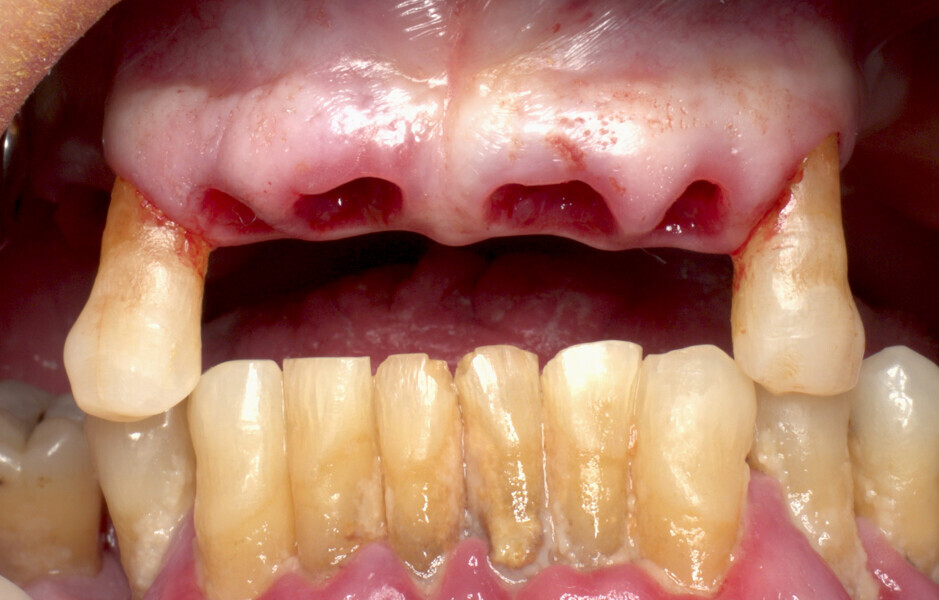

The fully digital Pro Arch protocol